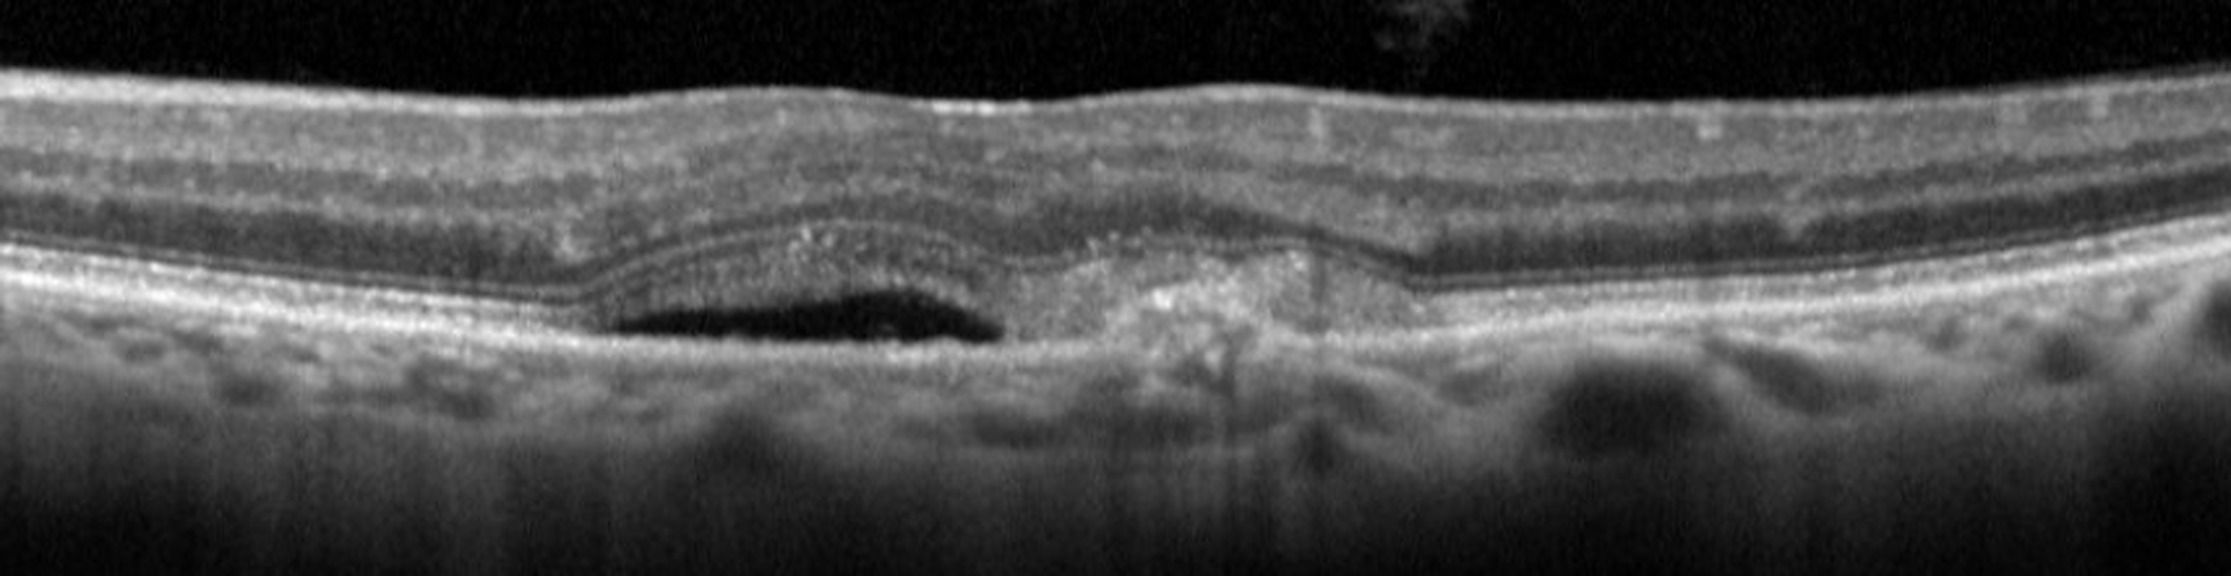

La réalisation d’une tomographie par cohérence optique OCT est rapide, indolore, non invasive et permet d’obtenir des résultats reproductibles. L’OCT est donc devenu un examen de routine incontournable dans le diagnostic et suivi des lésions liées à la DMLA. Les technologies récentes permettent de visualiser avec précision l’existence de ces anomalies, de préciser également leurs topographies et même de les quantifier.

Savoir reconnaître les différentes formes de la DMLA en OCT

Analyser le suivi des patients DMLA en OCT